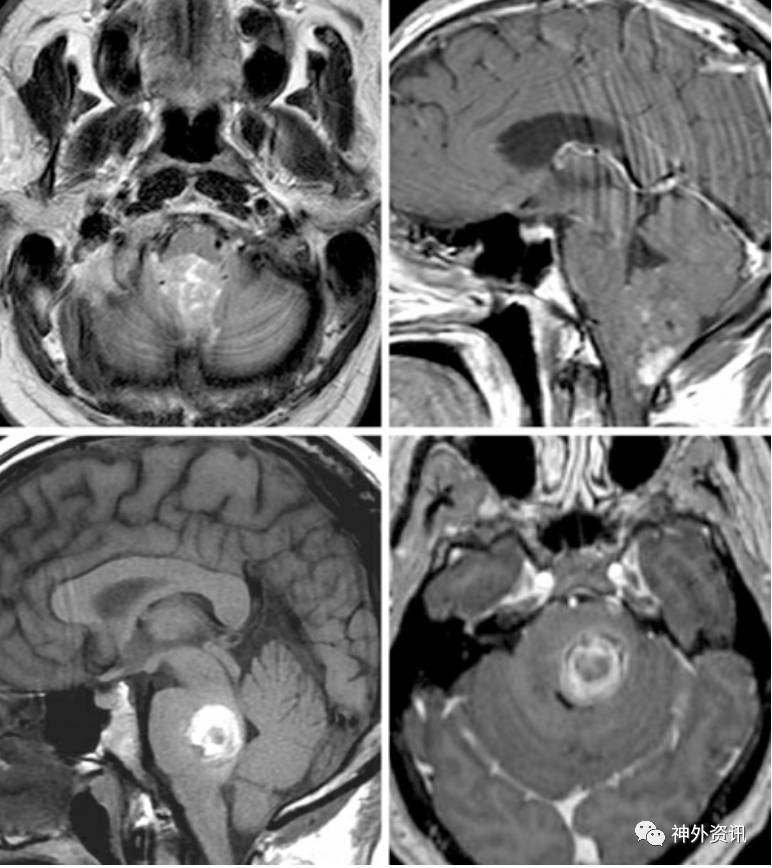

图3. 四脑室室管膜瘤部分钙化/强化(上方图像)。肿瘤和四脑室底的紧密关系决定是否在四脑室底留一薄片肿瘤组织。桥脑海绵状血管瘤(下方图像)要求在电生理监测面神经核之下切除占位。两个病例均采用膜帆入路。